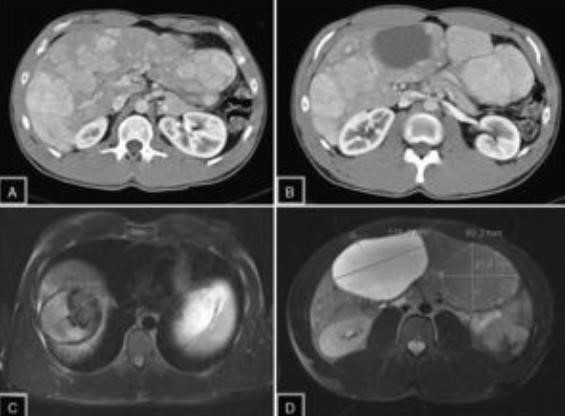

El principal factor de riesgo para su desarrollo es la cirrosis, principalmente la relacionada con la hepatitis viral crónica. Es este caso la hepatitis C, cirrosis alcohólica, cirrosis causada por hemocromatosis y cirrosis biliar primaria. La mayor parte de los casos en esta zona están relacionados con el virus de la hepatitis B, asociado o no con aflatoxina (micotoxinas producidas por dos especies de Aspergillus, un hongo localizado en especial en zonas con climas cálidos y húmedos). En el estudio de tomografía multicorte con técnica multifase el carcinoma hepatocelular (CHC) tiene vascularización predominantemente arterial, lo que determina un patrón de comportamiento específico caracterizado por un intenso reforzamiento en fase arterial, seguida de un lavado (washout) rápido en fase venosa portal, y en muchos casos la presencia de una seudocápsula en fases tardías. Este patrón ha resultado ser específico para el diagnóstico de carcinoma hepatocelular.(17-18)

El CHC presenta una vascularización predominantemente arterial (por neovascularización) a medida que avanza el proceso de hepatocarcinogénesis, a diferencia del parénquima hepático, en donde la vascularización es mixta: arterial y portal. Este patrón característico, favorecido por la alta probabilidad del CHC en pacientes con hepatopatía crónica, ha mostrado una especificidad próxima al 100% para el diagnóstico de CHC. No obstante, este patrón vascular está penalizado por una sensibilidad del 60%-70% en lesiones de pequeño tamaño, y se ha descrito que alrededor de un 15% delos CHC de pequeño tamaño son hipovasculares al no haber desarrollado aún su neovascularización, sin que ello indique que estas lesiones tengan un comportamiento menos agresivo.(18-21) No obstante, en ocasiones el carcinoma hepatocelular puede ser hipovascular y no mostrar reforzamiento intenso en la fase arterial, siendo en estos casos muy importantes las fases venosas portal y venosa tardía, en donde la lesión permanece hipodensa o incluso puede presentar un comportamiento atípico con importante reforzamiento en la fase arterial y ausencia de lavado tardío (Anexos 10 y 11).

Las recomendaciones estándar para el diagnóstico de CHC incluyen TC multifásica o RMN, que son modalidades beneficiosas para resaltar características únicas de CHC (Anexos 12 y 13). Las diferencias fisiológicas en la perfusión sanguínea entre lesiones hepatocarcinogénicas y tejido no neoplásico muestran diferencias distintivas en las características de imagen utilizando exámenes de contraste multifásico.(23) Las fases consisten en arterial hepática tardía (20-40 s), venosa portal (60-90 s) y retardada (35 min). La fase arterial tardía es útil para detectar lesiones hipervasculares con lesiones de CHC que realzan característicamente en relación con el parénquima hepático circundante. El realce de la lesión arterial se puede apreciar dentro de lesiones tan pequeñas como 1 cm. Dentro de las fases venosa portal y retardada, se observa comúnmente lavado o hipointensidad para las lesiones de CHC. Durante la fase retardada o de equilibrio, se pueden visualizar otras características de CHC como características de la cápsula (p. ej., lavado de la lesión con realce de seudocápsula) y arquitectura en mosaico. La introducción de agentes de contraste basados en gadolinio (gadobenato de dimeglumina y ácido gadoxetato) puede ayudar a la categorización LI-RADS.(19) Estos agentes son absorbidos por los hepatocitos del parénquima hepático normal y hay poca absorción en hepatocitos no funcionales o disfuncionales, como el caso del CHC. Los agentes basados en gadolinio funcionan de manera similar a los agentes extracelulares, pero pueden ayudar en el diagnóstico de lesiones con características atípicas (p. ej., sin lavado, hiperrealce arterial) o distinguir el CHC de las seudolesiones. Por ejemplo, estos agentes permiten una fase hepatobiliar posterior al contraste adicional, que mostrará una mayoría de lesiones de CHC (90%-95%) como hipointensas en relación con el parénquima hepático hiperintenso circundante.(23)